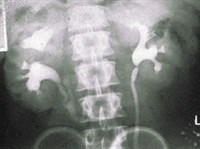

ПИЕЛОГРАФИЯ

Пиелография (от греч. pyelos — корыто, лоханка и «графия») — метод

рентгенологического исследования

лоханок и чашечек

почки

после заполнения их

рентгеноконтрастным веществом

.